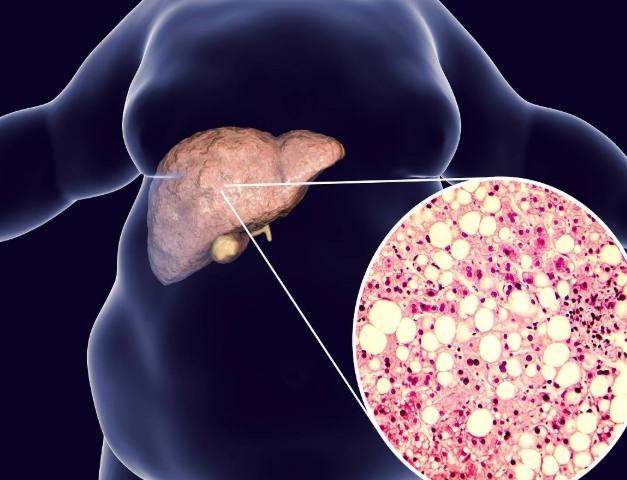

為什麼要知道自己的脂肪肝指數?因為脂肪肝現在太普遍了,幾乎成了現代人的國民病。但很多人覺得它不痛不癢,就放著不管。這其實很危險,脂肪肝是肝臟發炎、纖維化,甚至演變成肝硬化的前期階段。

我記得醫生跟我說,超音波雖然可以直接看到脂肪肝(肝臟看起來亮亮的),但那是一種比較主觀的分級(輕、中、重度)。而脂肪肝指數給的是一個具體數字,方便追蹤變化。

如果指數大於等於60,那就是紅燈了。強烈建議去找腸胃肝膽科醫生報到,做個超音波看清楚肝臟的狀況。這時候肝臟很可能已經有明顯的脂肪浸潤。

有個常見的迷思要打破:脂肪肝指數正常,不代表一定沒有脂肪肝。反之,指數超標,也未必100%有脂肪肝。這些指數是「預測模型」,不是診斷工具。最終的診斷還是要靠超音波等影像檢查。但指數異常絕對是一個必須正視的強烈信號。